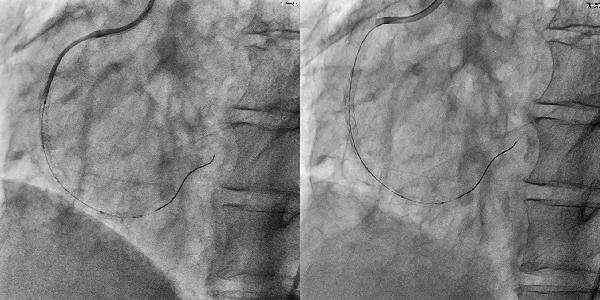

左 SCORE PRO Advance 透視画像 7.5fps

右 SCORE PRO Advance 撮影画像 15fps

撮影よりも低線量の透視において,更に半分のフレームレートでも十分な視認性を確保している。